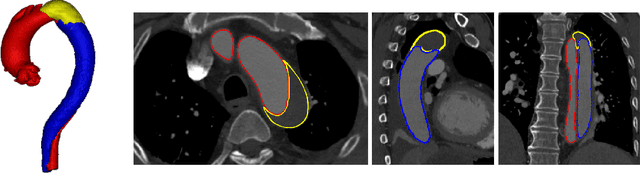

Abstract:Type-B Aortic Dissection (TBAD) is one of the most serious cardiovascular events characterized by a growing yearly incidence,and the severity of disease prognosis. Currently, computed tomography angiography (CTA) has been widely adopted for the diagnosis and prognosis of TBAD. Accurate segmentation of true lumen (TL), false lumen (FL), and false lumen thrombus (FLT) in CTA are crucial for the precise quantification of anatomical features. However, existing works only focus on only TL and FL without considering FLT. In this paper, we propose ImageTBAD, the first 3D computed tomography angiography (CTA) image dataset of TBAD with annotation of TL, FL, and FLT. The proposed dataset contains 100 TBAD CTA images, which is of decent size compared with existing medical imaging datasets. As FLT can appear almost anywhere along the aorta with irregular shapes, segmentation of FLT presents a wide class of segmentation problems where targets exist in a variety of positions with irregular shapes. We further propose a baseline method for automatic segmentation of TBAD. Results show that the baseline method can achieve comparable results with existing works on aorta and TL segmentation. However, the segmentation accuracy of FLT is only 52%, which leaves large room for improvement and also shows the challenge of our dataset. To facilitate further research on this challenging problem, our dataset and codes are released to the public.